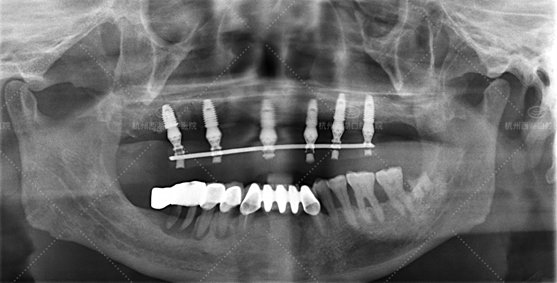

手术时间:14:00—14:30

术后CBCT照如下

当天即拔即种,宋叔叔有了新牙很开心,立马和家人分享喜悦,也很想让自己的夫人换上新牙。